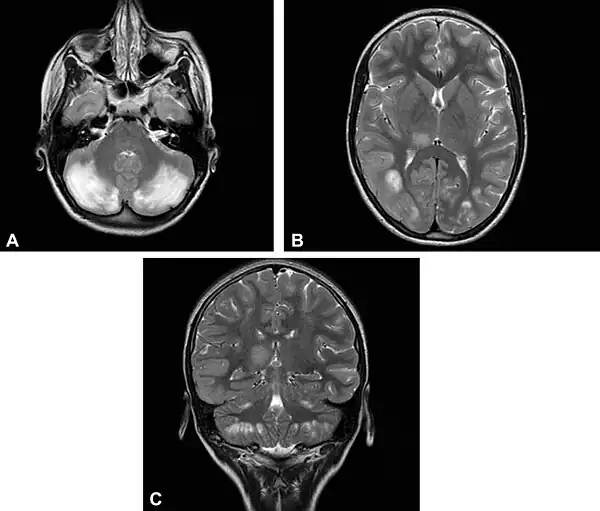

Иллюстрации